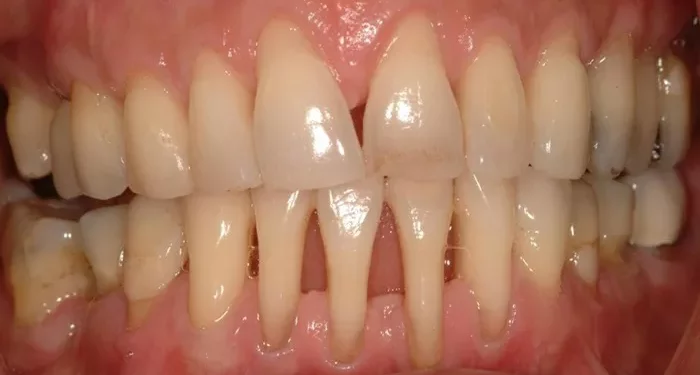

This case report explores the management of a female patient presenting with severe gingival recession, accompanied by dentinal hypersensitivity. The condition significantly impacted her ability to perform optimal oral hygiene and comfortably consume hot or cold foods. The patient’s clinical presentation, with receding gums and a denuded root surface, was effectively treated using the double pedicle flap technique, which not only restored keratinized tissue but also alleviated the hypersensitivity and provided satisfactory root coverage.

Gingival recession, characterized by the displacement of the gingival margin beyond the cementoenamel junction, is a common condition resulting from periodontal disease and poor oral hygiene. Other contributing factors include the patient’s gingival biotype, tooth morphology, dental alignment, frenum attachment, and alveolar bone dehiscence, all of which can exacerbate the risk of recession.